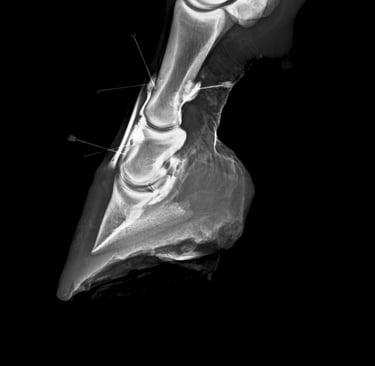

DIAGNOSTICO POR IMAGENES: ECOGRAFIA Y RADIOGRAFIA